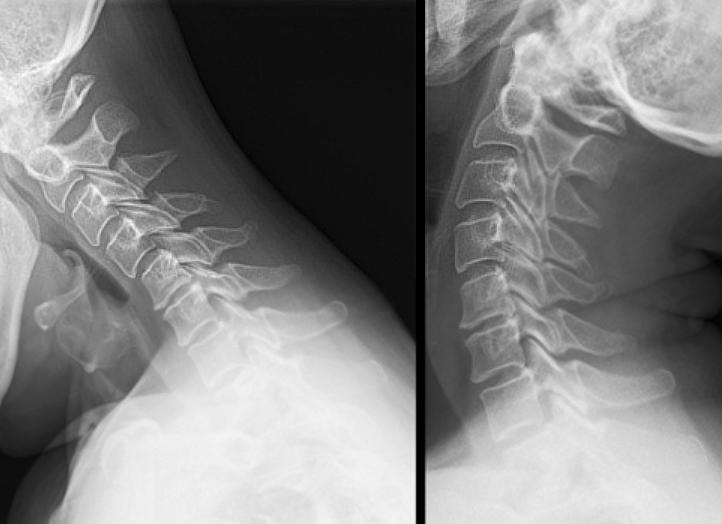

• рентгенография. На снимках хорошо видны аномалии строения шейной зоны (состояние позвонков, их размер, наличие сращений). Исследование проводится при полном сгибании/разгибании шеи для оценки стабильности позвоночника;

В первую очередь проводят неврологическую оценку подвижности шейного отдела (наклоны головы вперед-назад, вправо-влево, вращение головы). Затем назначают рентгенографию шейного отдела в двух проекциях, важно провести исследование в положении полного сгибания и разгибания шеи, дабы иметь возможность определить нестабильность шейного отдела позвоночника.

На основании рентгеновских снимков можно будет увидеть, почему шея короткая и по какому типу произошла деформация шейного отдела хребта.

Сращение шейных позвонков видно на рентгене

Рентгенографическое исследование осуществляется в двух проекциях, проводится на верхнегрудном и шейном отделах позвоночника. С помощью процедуры можно определить тип заболевания.